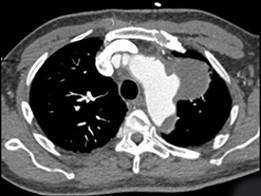

问题 男,50岁,胸背剧痛一周余,CT如图,最可能的诊断是 ( )

选项 A、左上肺癌并侵犯主动脉弓部 B、纵隔肿瘤 C、主动脉弓假性动脉瘤 D、主动脉弓夹层动脉瘤 E、主动脉弓真性动脉瘤

答案 C